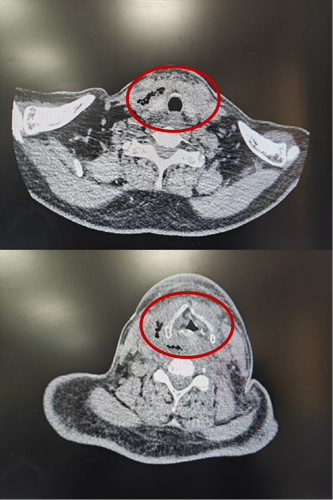

患者甲CT示:颈部及纵隔脓肿,脓肿中含有多个气腔

2月15日、2月20日,当长沙沉浸在辞旧迎新的欢声笑语中,两位病情凶险的颈部深部脓肿患者先后被推入耳鼻咽喉头颈外科。他们都有多年糖尿病病史,春节期间饮食不规律、作息紊乱、血糖波动大,让原本隐匿的感染如野火般迅速蔓延。其中一位患者的感染已突破颈部间隙,如藤蔓般向下侵入纵隔区域——那里是心脏、大血管、气管的“交通枢纽”,是人体最脆弱的生命禁区之一。CT影像上,脓肿中密布的气腔像一个个危险的信号,气管严重受压,每一次呼吸都变得艰难。而临床研究数据表明,颈深部脓肿并发下行性纵隔炎,病死率为40%~70%。患者的生命,危在旦夕。